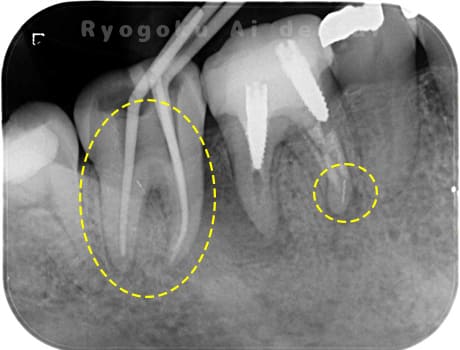

- 重度カリエス

- 抜髄治療、マイクロエンド

- 99,000円

虫歯が大きく、神経の保存ができなかったため、マイクロエンド治療を行いました。